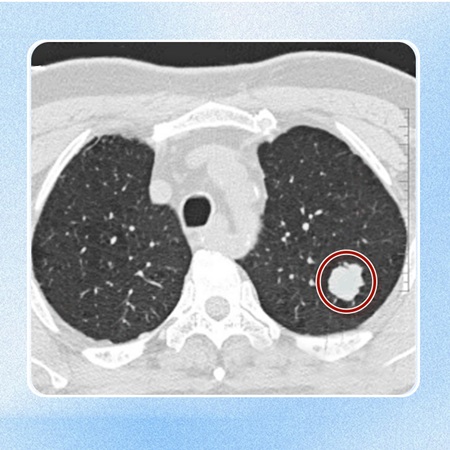

实际上,神经内分泌肿瘤并不具备显著的特异性症状,这主要归因于其缓慢的进展速度和人体对其较高的耐受性。许多患者仅在例行体检中偶然发现肺部或胸腺存在占位性病变后,方才意识到问题并寻求医疗帮助。

至于非功能性神经内分泌肿瘤,患者可能仅体验到咳嗽、咳血等较为普遍的症状。当肿瘤体积增大或位置特殊,如直接位于主支气管上并造成压迫时,还可能导致肺不张,进而缩减了有效的呼吸面积,影响肺功能,使患者呼吸受阻。